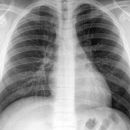

Thorax p.-a.

Streng symmetrisch, Schulterblätter außerhalb der Lunge. Atemphase: maximale Inspiration. Bei Verdacht auf Pneumothorax in maximaler Expiration die Aufnahme durchführen.

Abgebildet müssen sein: beide Lungenflügel, PC-Winkel und Lungenspitzen. Die ersten 3-5 Rippen sollten schwach erkennbar sein, die inneren Scapularänder sollten außerhalb des Thorax liegen.